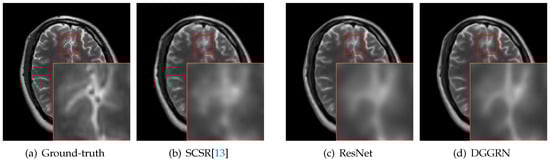

4.3. Comparison with State-of-the-Art Methods

5. Discussion